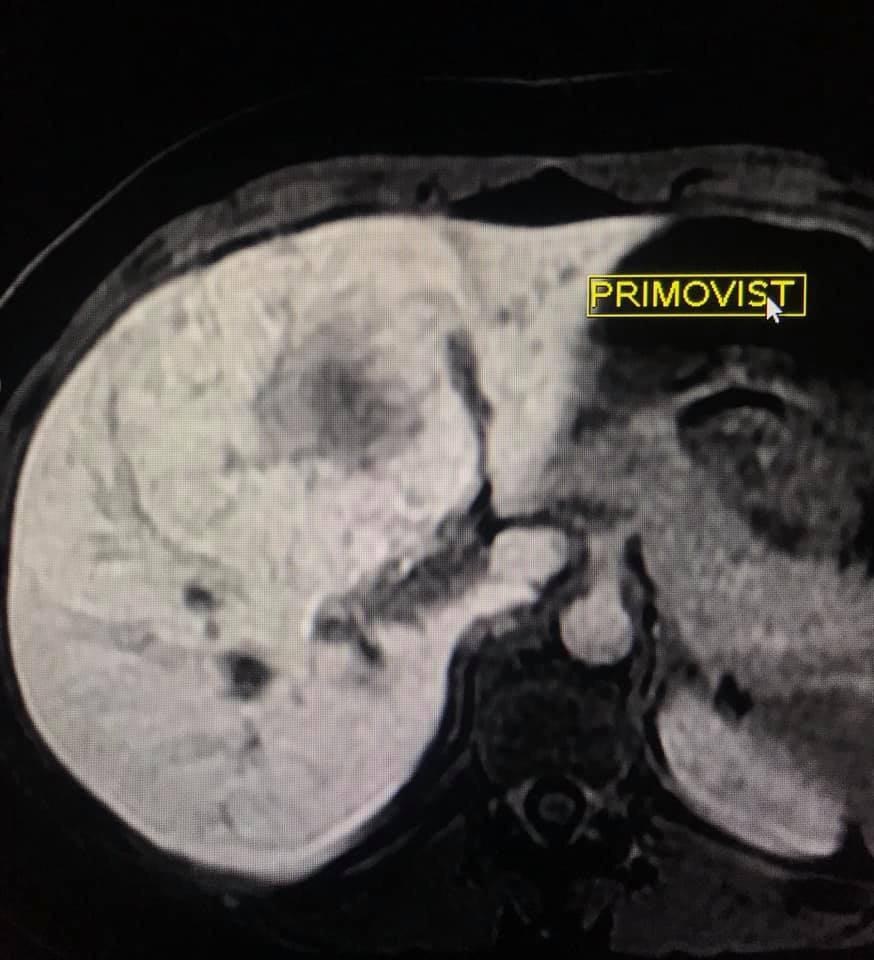

La evaluación hepatica entre Adenoma y HNF por resonancia magnética y su diferenciación con hepatocarcinoma puede ser difícil en ciertos casos aún, con el uso de contraste hepato especifico.

Se presenta caso de paciente de la 3a década, que en su embarazo se diagnostica con sospecha de adenoma y posterior al embarazo se realiza estudio de control contrastado para su mejor diferenciación.

en este caso, aún cuando los hallazgos son atípicos tanto para hiperplasia nodular focal como para adenoma, nos inclinamos hacia el diagnóstico de adenoma debido a los antecedentes de la paciente, el tamaño de la lesión, el área de sangrado, el contenido de grasa.